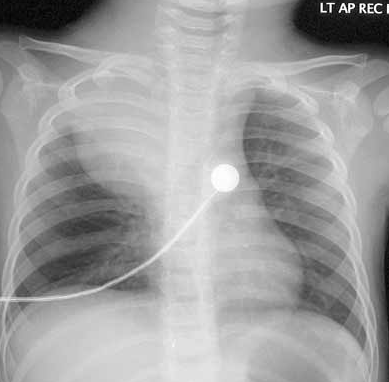

DISCUSSION: In addition to the lateral neck mass, physicians in the emergency department noted dilated superficial vessels on the right anterior chest wall (Figure 1). A chest radiograph demonstrated a large density in the right upper lobe with a mediastinal shift to the left side (Figure 2).

The diagnosis of an infected cystic hygroma can be difficult because other processes—including retropharyngeal abscesses and infected branchial cleft cysts—also present with a neck mass, fever, and stridor. In many cases, advanced imaging is necessary to confirm the diagnosis. CT or MRI of a cystic hygroma typically reveals a multiloculated cystic mass. CT can delineate the size of the mass, although MRI more reliably identifies extension into the soft tissues, particularly neurovascular structures.In the presence of trauma or an upper respiratory tract infection, a cystic hygroma often becomes infected and grows rapidly, a process that produces fever and pain. Infiltration of the mass into the floor of the mouth, base of the tongue, epiglottis, or mediastinum can compromise the airway. This rapid enlargement of the mass secondary to infection accounts for the clinical signs and symptoms. In addition, our patient's clinical findings were consistent with superior vena cava syndrome (venous congestion, dysphonia, dyspnea, and dilated chest wall veins), which eventuated from thoracic compression of the hygroma (Figure 3).